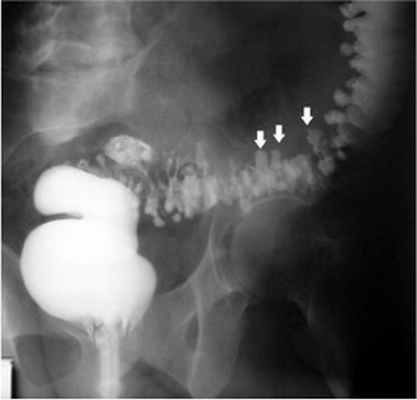

Клинические проявления дивертикулеза толстой кишки и его осложнений не могут служить основанием для установления точного диагноза заболевания. Диагностика и дифференциальная диагностика дивертикулеза толстой кишки основывается на анализе клинических проявлений заболевания и результатах обязательного рентгенологического и эндоскопического исследований толстой кишки.

- Ирригоскопия - рентгеновское исследование, при котором производят наполнение просвета толстой кишки контрастной взвесью и оценивают ее состояние при наполнении и после опорожнения кишки.